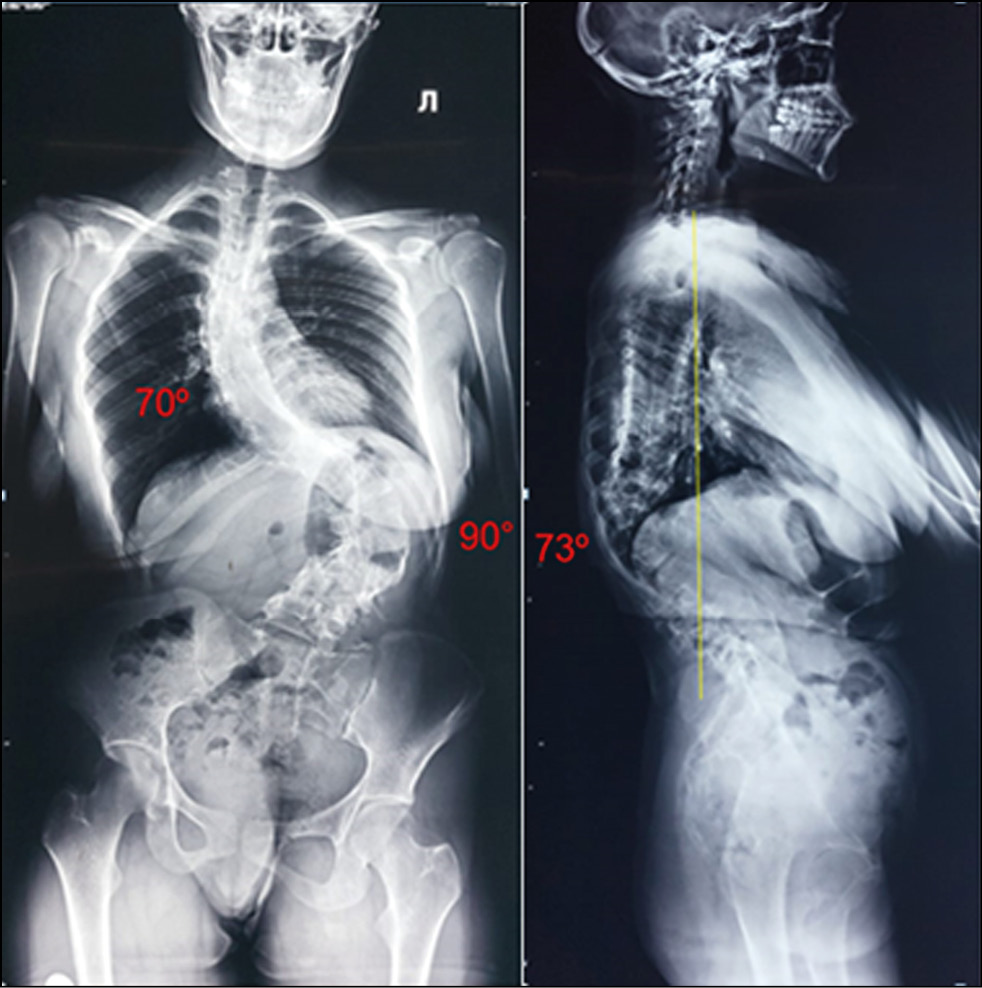

Postural spondylograms revealed left-sided thoracolumbar degree IV kyphoscoliosis, with a scoliotic deformity angle of 70° in the thoracic region, 90° in the lumbar region, local kyphosis angle of 73° in the thoracolumbar transition, and 5.7 cm of negative sagittal imbalance (SVA, sagittal vertical axis) (Fig. 1).

Fig. 1. Postural spondylograms upon admission.